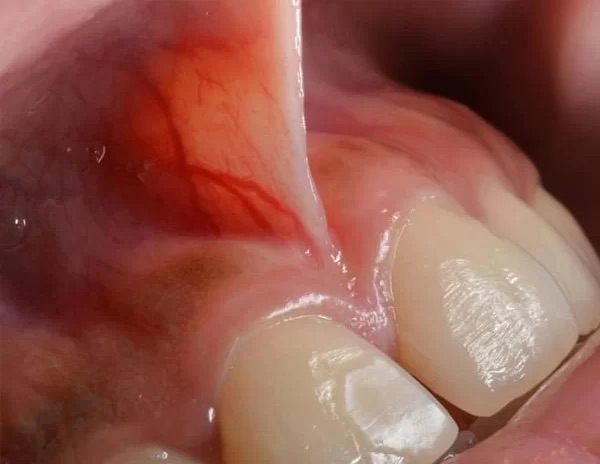

Frenulum diş əti toxuması ilə dil, dodaqlar və yanaq arasında yerləşən, bu toxumaları bir-birinə bağlayan və hərəkətlərini məhdudlaşdıran yumşaq selikli qişadır.

Frenulum tez-tez ağızda, yuxarı və aşağı mərkəzi kəsici dişlərimiz arasında, yanaqlarımız və arxa dişlərimiz arasında və dilimizin altında olur.

Frenulumlar, xüsusilə normaldan daha böyük və qalın olduqda və dişin kənarına çox yaxın bağlandıqda, diş ətini aşağı çəkərək diş ətinin çəkilməsinə və diş əti xəstəliyinə səbəb ola bilər. Dildə daha böyük və qalın olan frenulumlar xüsusilə kiçik uşaqlarda nitq problemlərinə səbəb ola bilər.